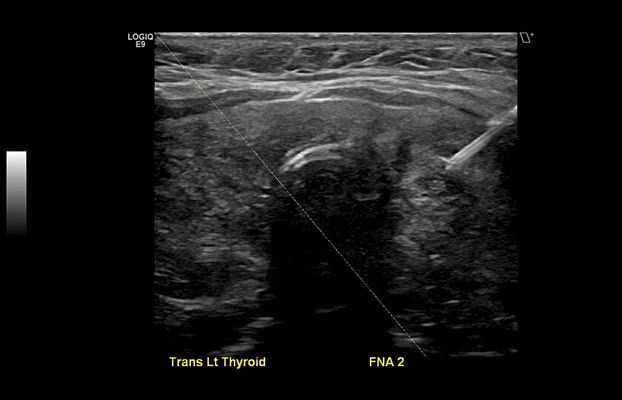

Клинические изображения

- Thyroid Productivity Package - программный протокол для маркировки, учета, измерения и описания узлов и образований в щитовидной железе.

- V Nav Needle Tip Tracking Starter Kit 16/18GA - набор Needle Tip Tracking для точного определения положения и коррекции направления пункционной иглы, размер игл 16/18GA. Включает в себя многоразовый сенсор и 5 комплектов стерильных одноразовых игл, стилетов и чехлов.

- V Nav Needle Tip Tracking Starter Kit 18/20GA - набор Needle Tip Tracking для точного определения положения и коррекции направления пункционной иглы, размер игл 18/20GA. Включает в себя многоразовый сенсор и 5 комплектов стерильных одноразовых игл, стилетов и чехлов.

- V Nav Virtual Needle Tracking Starter Kit - набор Virtual Needle Tracking для виртуального определения положения и коррекции направления пункционной иглы. Включает в себя многоразовый сенсор и 5 комплектов стерильных одноразовых игл и навигаторов.

- Протокол объемных образований щитовидной железы — программа для маркировки, учета, измерения и описания узлов и образований в щитовидной железе.